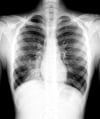

Правосторонняя нижнедолевая пневмония

Такая рентгенография грудной клетки показывает наличие инфильтрата, который не затемняет правую границу сердца (т.е., признак "утраты контура" отсутствует). Поскольку признак "утраты контура" развивается, когда 2 примыкающие структуры имеют сходную рентгенконтрастность, доля легкого, пораженная этим инфильтратом, не соприкасается с правой границей сердца, т.е. является правой нижней долей.